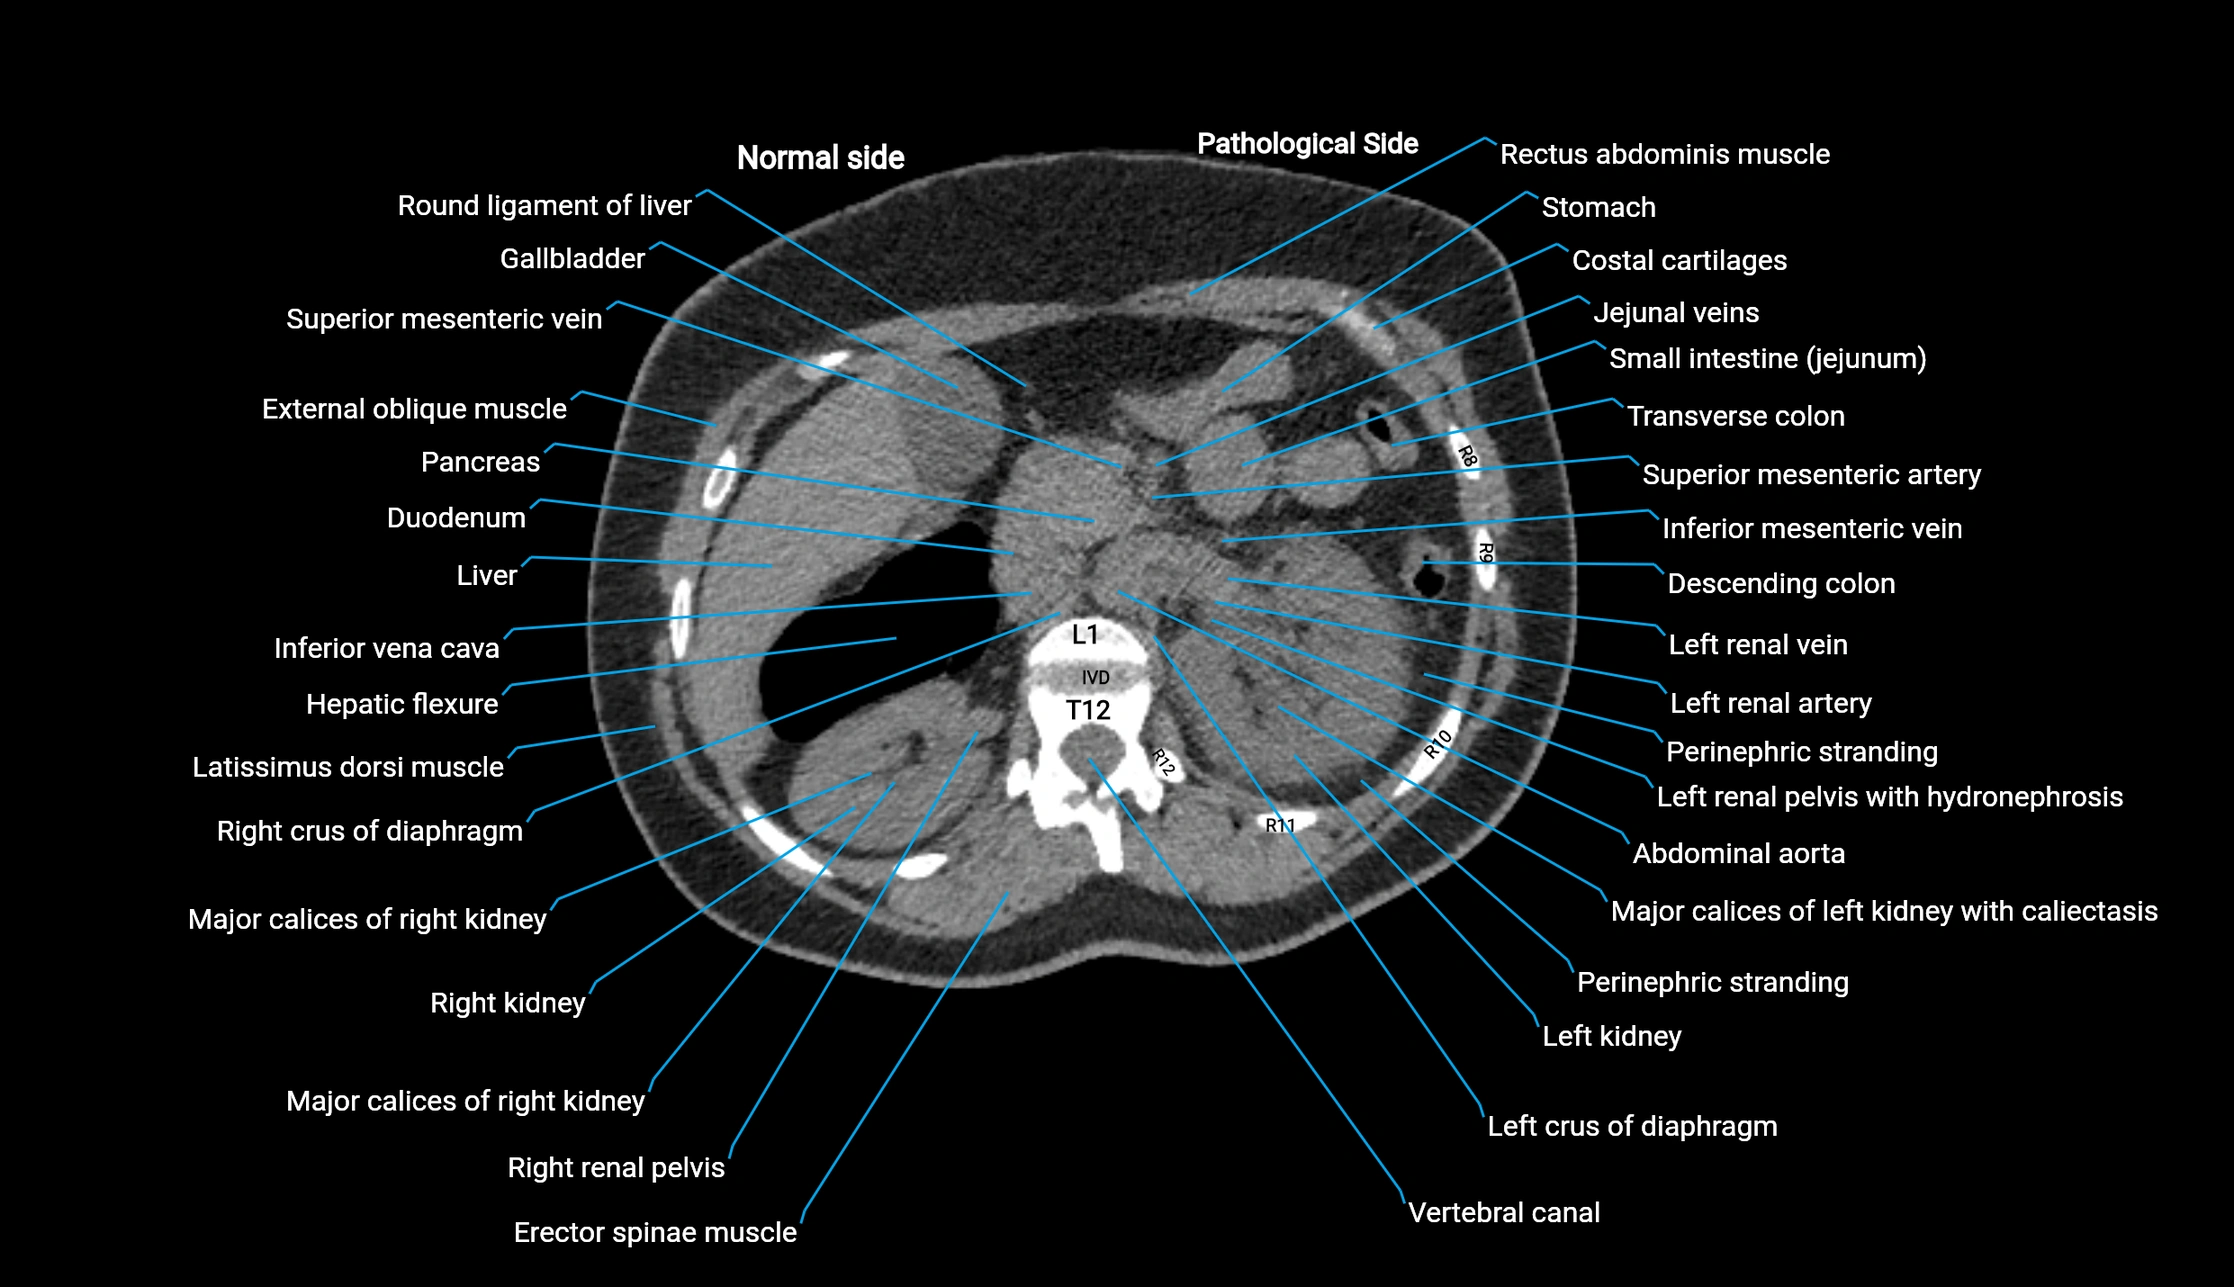

CT image

image